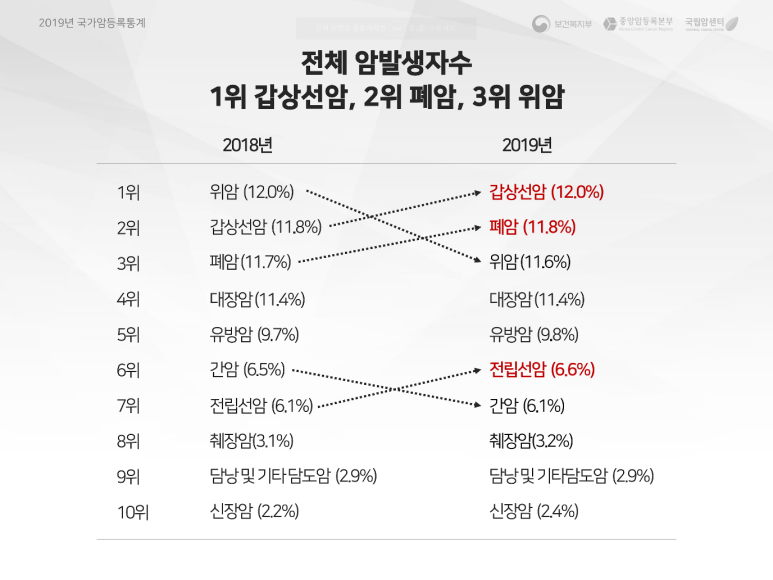

용인항유외과 유방갑상선센터 진료실과 초음파실 갑상선암 검진을 왜 해야 하나요?먼저 통계를 보면 갑상선암은 우리나라에서 가장 발생률이 높은 암으로 발표됐습니다.(2019년 국가암등록통계-2021/12/29 중앙암등록부 발표)

국가암등록통계자료

전체 암 발생자 수를 보면 1위 갑상선암, 2위 폐암, 3위 위암 순으로 발병할 것으로 보입니다.